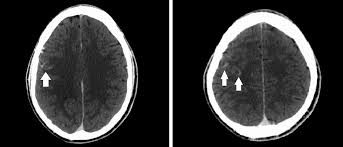

Dijital substraksiyon anjiografi sonrası subaraknoid kanamayı taklit eden baş ağrısı: olgu sunumu

Subaraknoid kanama (SAK) akut başlangıçlı, ani ve şiddetli baş ağrısı ile ortaya çıkan klinik bir durumdur. Baş ağrısına ilaveten ciddi bulantı, kusma, baş dönmesi, konfüzyon, ajitasyon, fokal nörolojik defisitler ve kan basıncı yüksekliği görülebilir. Kanamadan 6-24 saat sonra meningeal irritasyon bulguları bu klinik duruma eklenebilir.

Dijital substraksiyon anjiografi (DSA) diğer görüntüleme tetkiklerine ek olarak, vasküler anormalliklerin tanısı amacıyla, cerrahi veya endovasküler tedavi planlaması için kullanılmaktadır. İşlem sonrası %0.2-%4.5 oranında nörolojik komplikasyonlar görülebilmektedir. Ortalama % 50 hastada ise DSA işlemi sonrası baş ağrıları olabilmektedir.